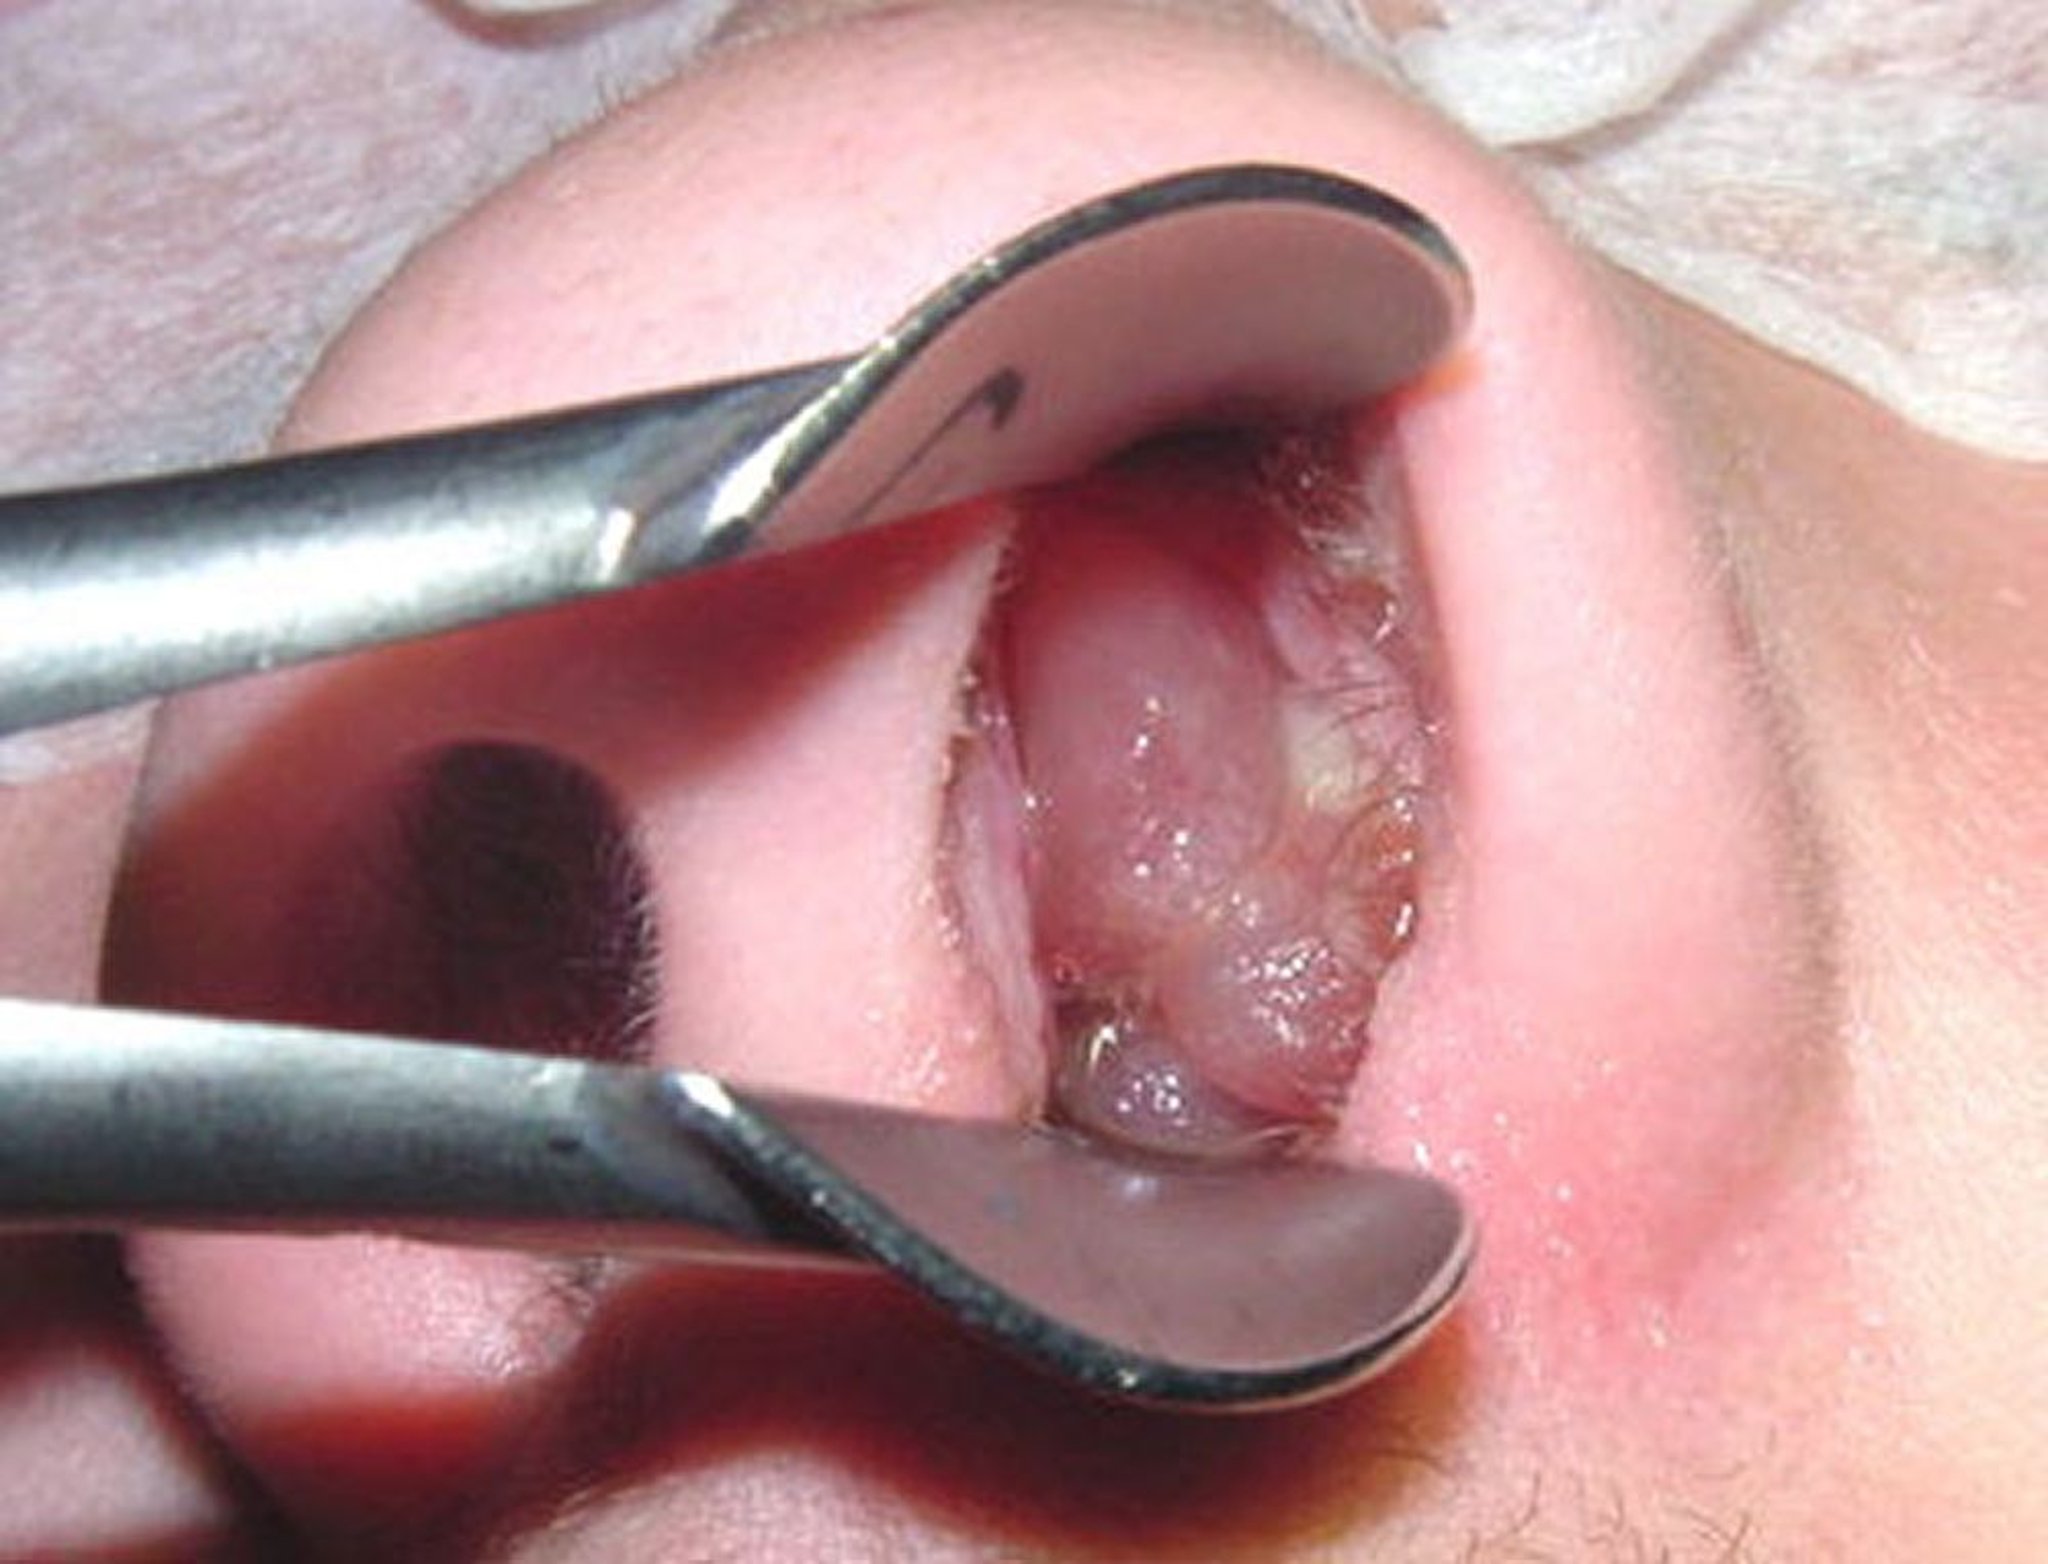

Polyps mũi trưởng thành có thể trông giống quả nho không hạt, đã bóc vỏ.

Hình ảnh được cung cấp bởi Bechara Ghorayeb, MD.